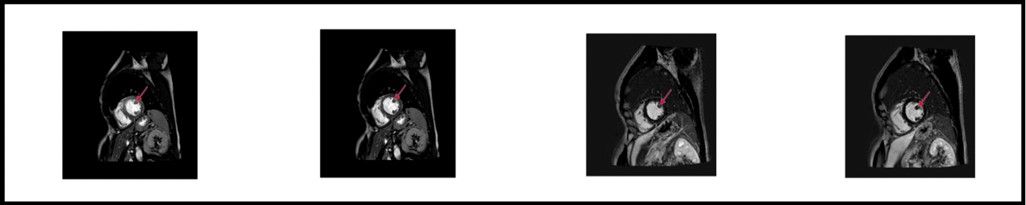

The cardiac magnetic resonance (CMR) detected an isolated late gadolinium enhancement (LGE) in the anterior papillary muscle of the left ventricle suggestive of a non-ischaemic endomyocardial fibrosis (Figure 5).

Figure 5: late gadolinium enhancement (LGE) in the anterior papillary muscle of the left ventricle on CMR